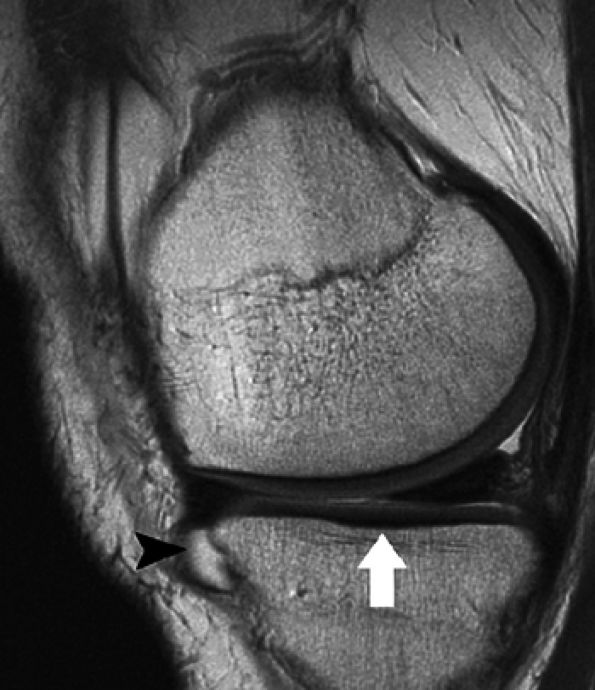

envelope, providing more efficient use of imaging time. Fast spin-echo images are cartilage-sensitive due to an inherent magnetization transfer contrast and exchange of off-resonance magnetization between slices, the net effect of which is to saturate the bound pool of hydrogen nuclei, resulting in a decrease in signal intensity from the free pool.36 This exchange results in relatively high signal intensity from fluid compared to the lower signal intensity of articular cartilage, providing an effective differential contrast among menisci, articular cartilage, and fluid in the meniscosynovial recesses (Fig. 7.5). With arthroscopy as a standard, Potter et al. found that articular surface evaluation using spin-echo sequences had a sensitivity of 87%, a specificity of 94%, and an accuracy of 92%, with minimal interobserver variability (kappa = 0.93).18 These findings of reproducibility support the use of MR imaging as a noninvasive and objective outcome measure of surgically manipulated cartilage and in the longitudinal evaluation of traumatic and degenerative cartilage lesions.

FIGURE 7.5 ● Sagittal fast spin-echo MR image of the knee in a 50-year-old patient demonstrates differential contrast for the high-signal-intensity joint fluid within the meniscosynovial recess (arrowhead), the intermediate signal intensity of hyaline cartilage, and the low signal intensity of meniscal fibrocartilage. Over the tibial plateau cartilage, note the gray-scale stratification (arrow) with lower signal intensity in the basilar components.